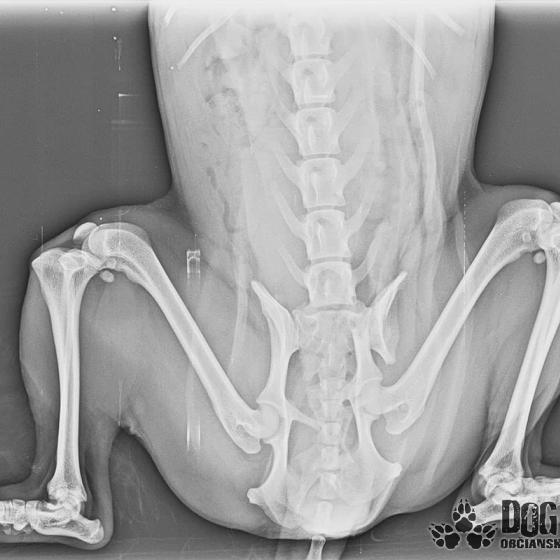

Bola neskutočne zanedbaná, hladná a dolámaná. Panvu má zlomenú na troch miestach, od úderu jej praskol močový mechúr a mala na sebe snáď všetky blchy sveta, žrali ju zaživa. Zotavuje sa.. Pomaličky, ale zotavuje sa po náročných operáciách a dúfame, že bude opäť v poriadku. Bude potrebovať rehabilitovať, aby vedela opäť behať, ale zabezpečíme jej úplne všetko, čo bude treba!!